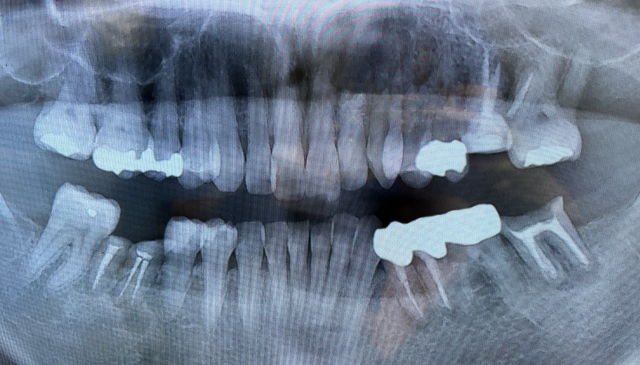

成人になってから歯並びが悪くなる原因のひとつに「歯周病」があります。

歯周病が進行すると、歯を支える骨が溶けて歯が動きやすくなり、前歯が出てきたり、すき間ができたりといった歯並びの乱れが生じます。

見た目だけでなく噛み合わせや清掃性にも影響します。

歯周病は自覚症状なく進行し、気づけば歯並びが悪化し、元の噛み合わせには戻らないことも。

手遅れになる前に定期検診で早期発見・早期治療を心掛けましょう。

欠損歯の放置

むし歯や歯周病で歯を失ったままにすると、残った歯に悪影響を与え、歯並びが変化します。

歯は空いたスペースを埋めようと動き、傾いたり、噛み合う歯が伸びたりすることも。

治療途中で中断したり、詰め物が取れたまま放置することも、歯並びの悪化に繋がります。